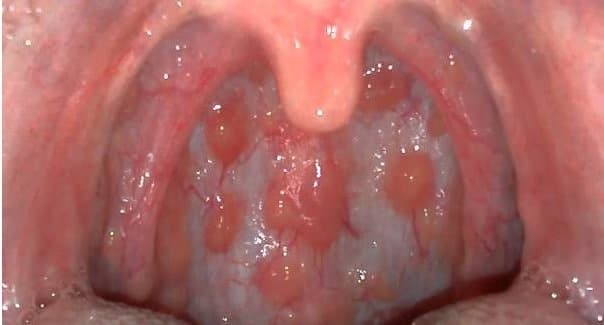

Viêm họng hạt là một dạng của viêm họng mạn tính, do tình trạng viêm họng kéo dài dẫn đến sự phát triển quá độ của các tổ chức lympho ở thành sau họng, từ đó tạo nên các hạt. Vậy thực tế, viêm họng hạt có nguy hiểm không? 1. Viêm họng hạt có […]